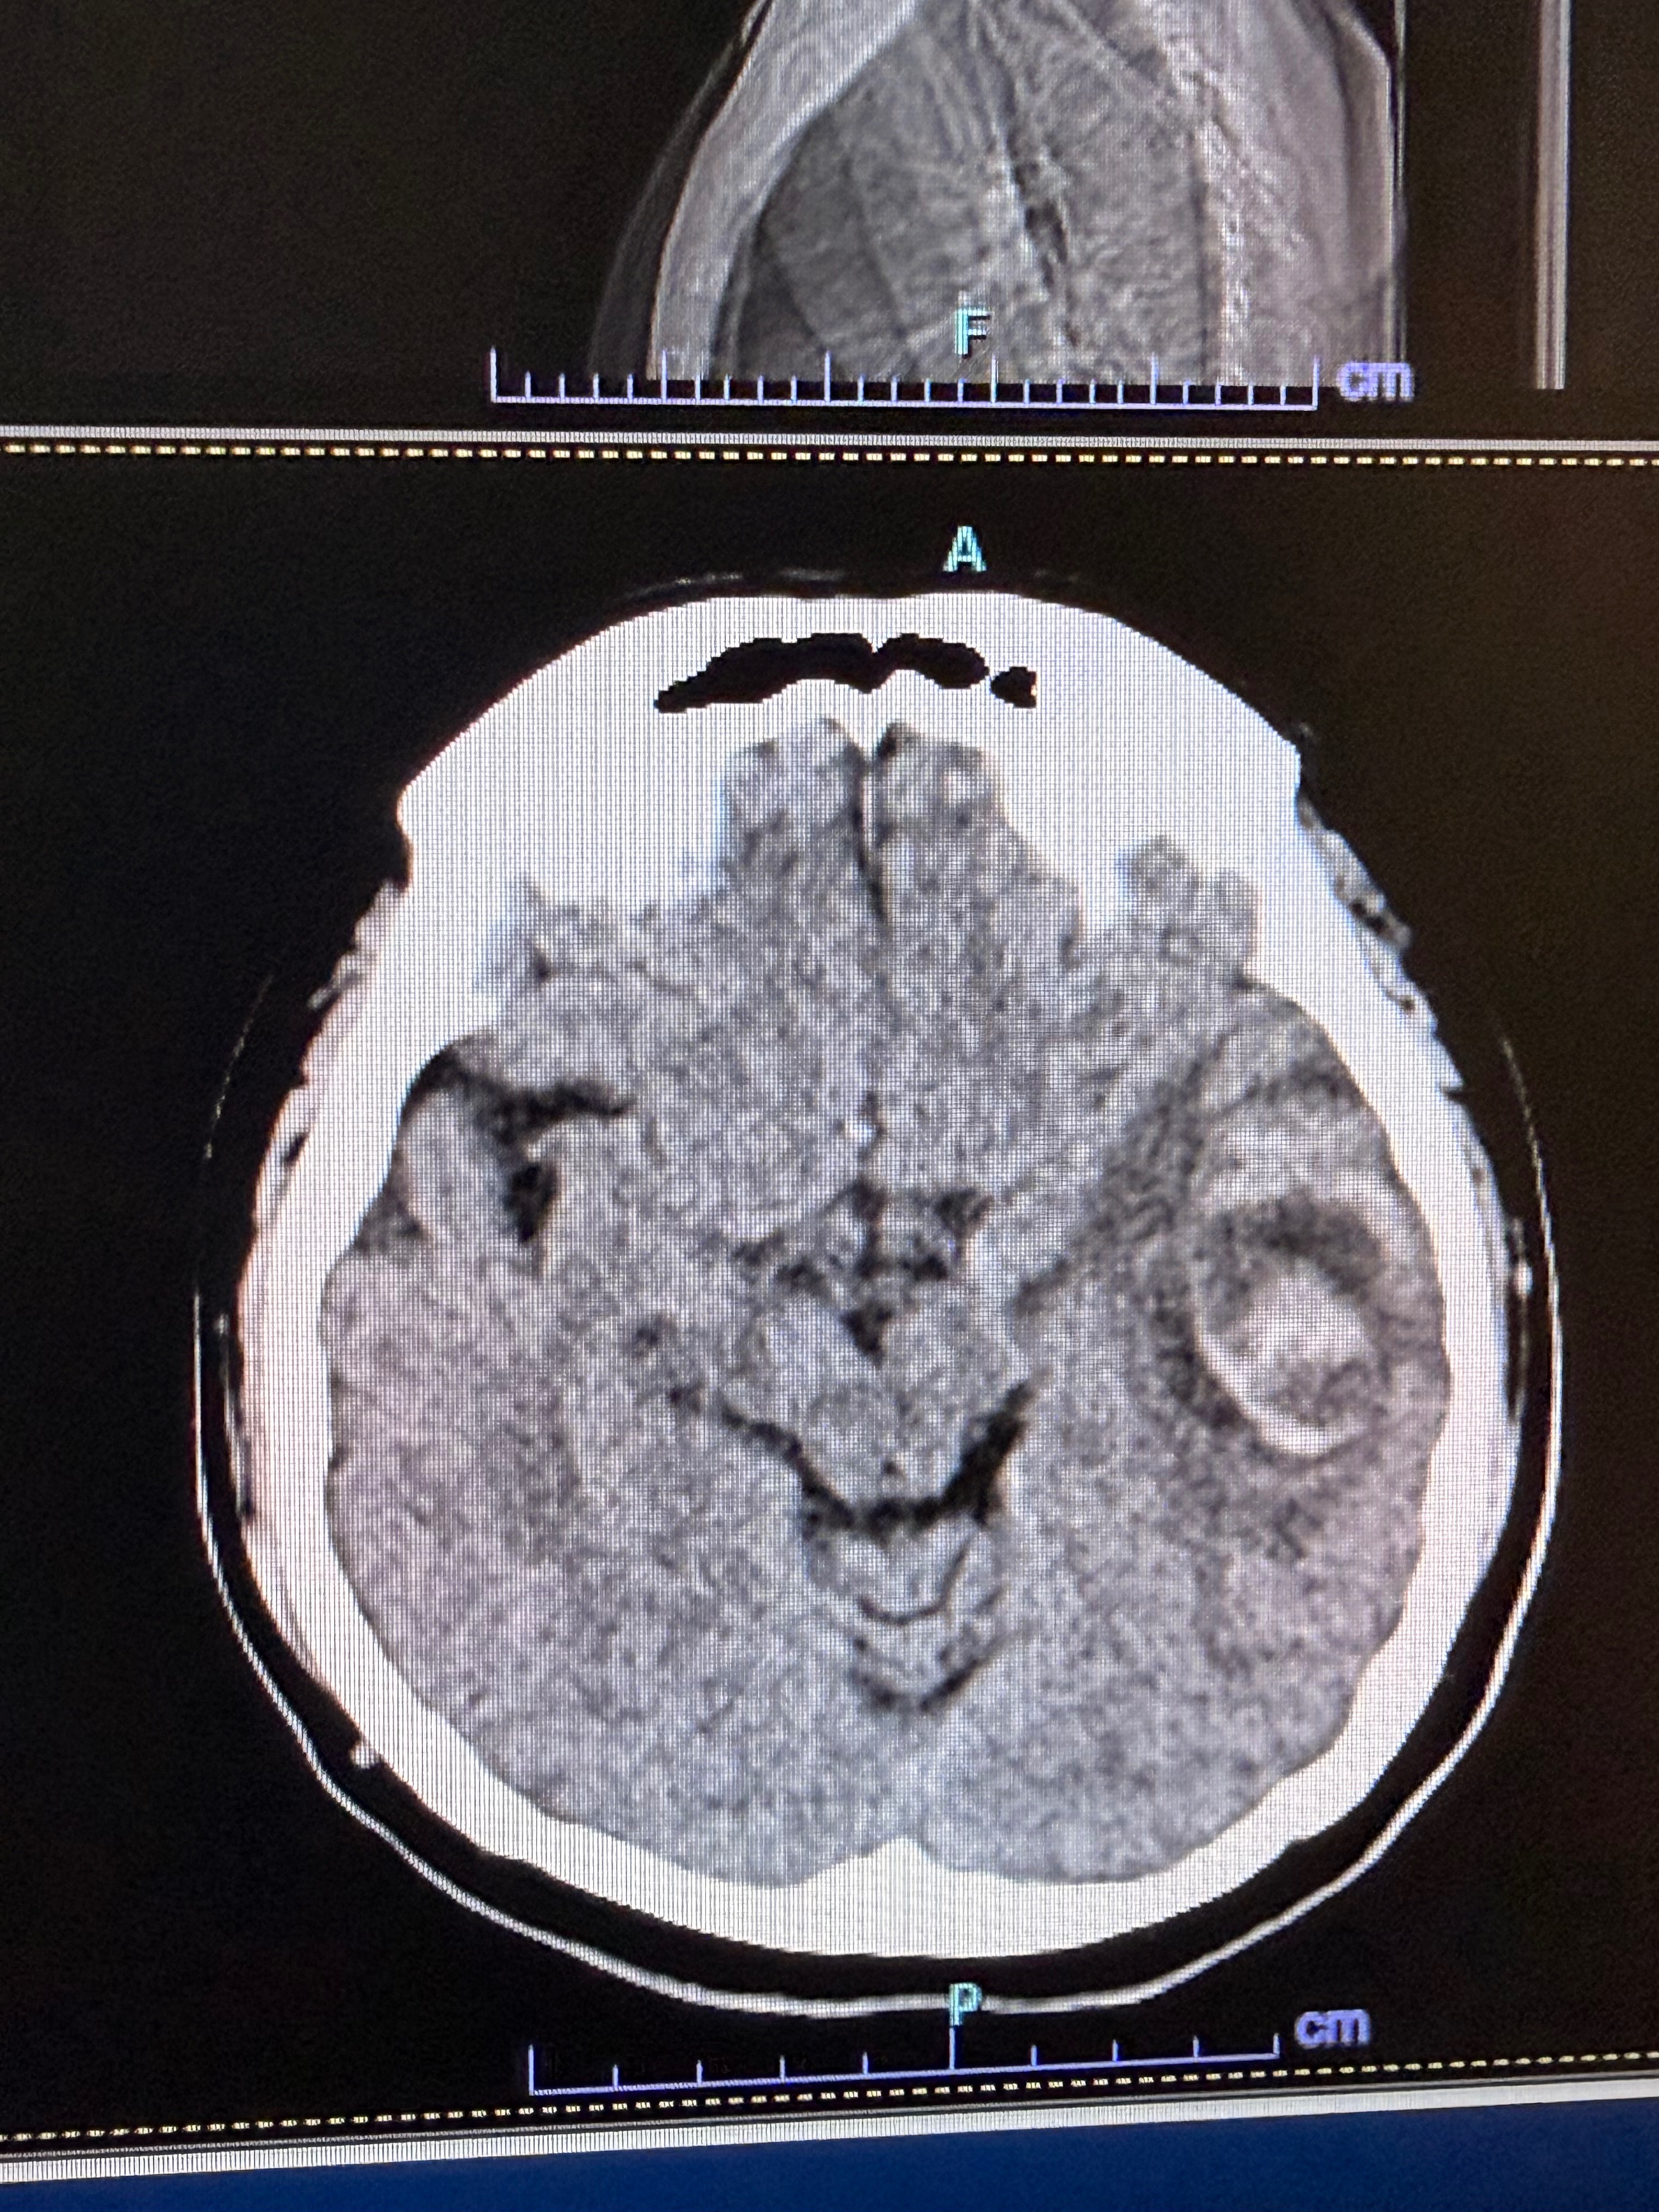

On December 19th, our family experienced a sudden medical emergency when our dad Abraham developed severe headaches and difficulty with speech. He was taken to the hospital where doctors discovered a large brain tumor that required immediate surgery. After the pathology results came back, doctors confirmed a diagnosis of terminal brain cancer, a high-grade stage IV glioblastoma.